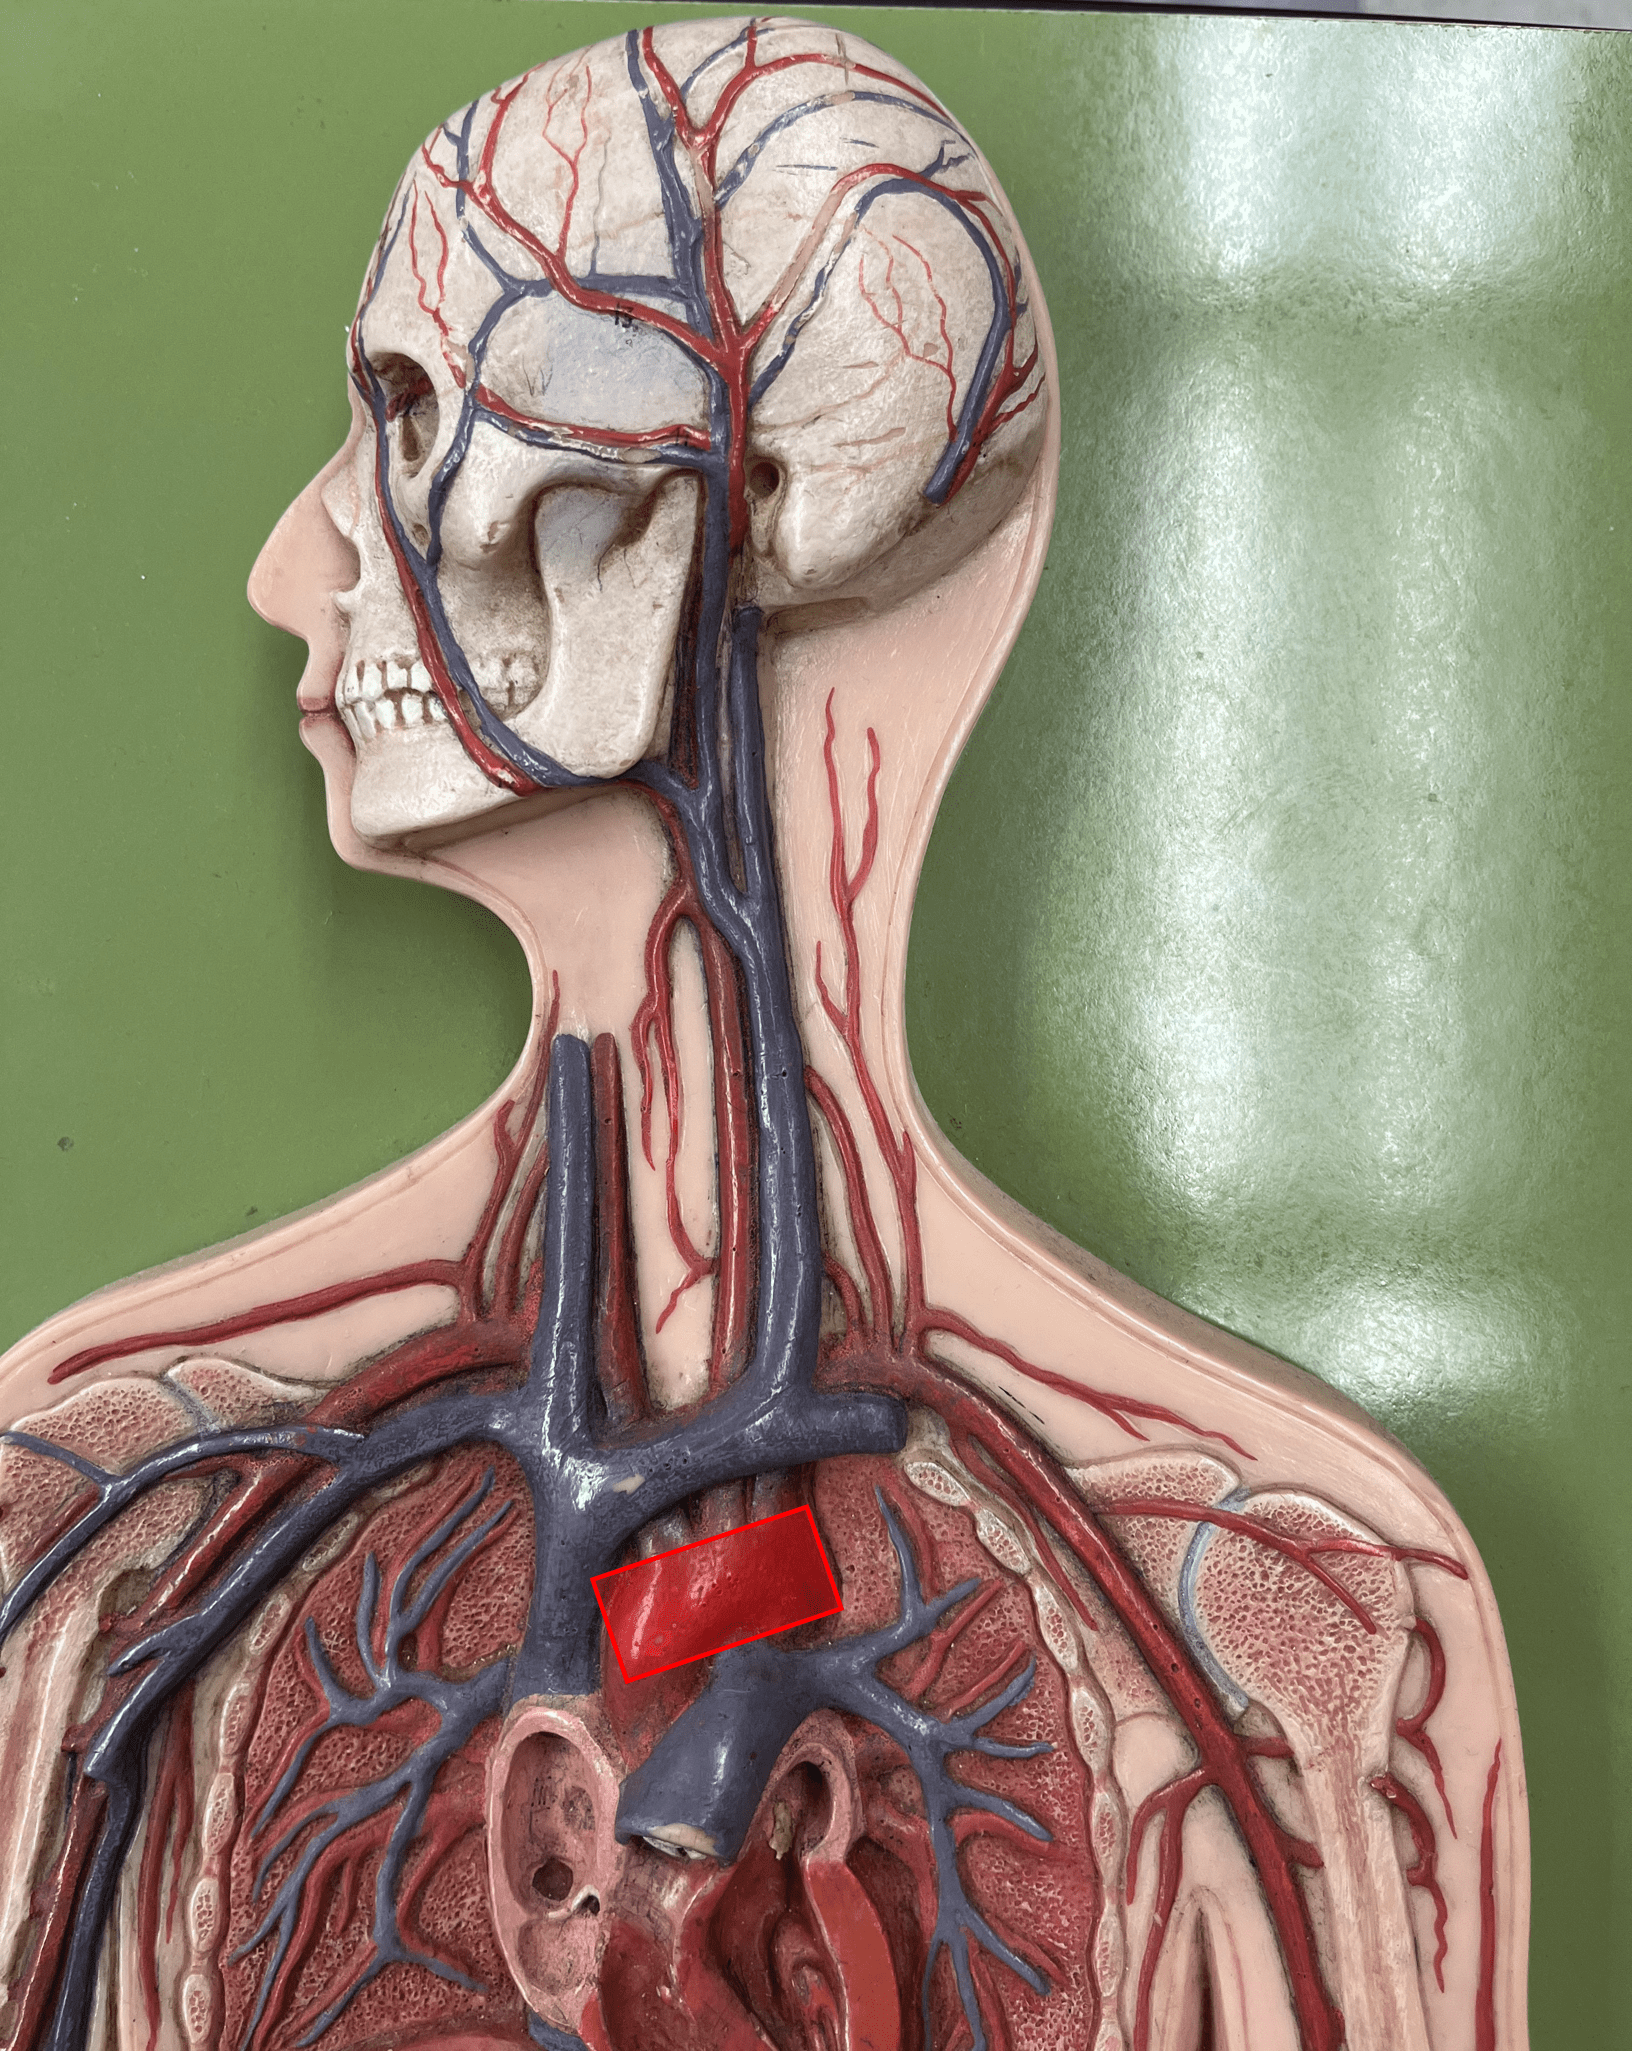

ascending aorta

• An artery of the thorax.

• Originates from the left ventricle of the heart.

• Supplies its branches.

• Originates from the left ventricle of the heart.

• Supplies its branches.

aortic arch

• An artery of the thorax.

• Originates as the continuation of the ascending aorta.

• Supplies its branches: the brachiocephalic trunk, L. subclavian artery, and L. common carotid artery.

• Originates as the continuation of the ascending aorta.

• Supplies its branches: the brachiocephalic trunk, L. subclavian artery, and L. common carotid artery.

brachiocephalic trunk

• An artery of the thorax.

• Originates from the aortic arch.

• Supplies its branches: the R. subclavian and R. common carotid arteries.

• Originates from the aortic arch.

• Supplies its branches: the R. subclavian and R. common carotid arteries.

thoracic aorta

• An artery of the thorax.

• Originates as the continuation of the aortic arch.

• Supplies its branches.

• Originates as the continuation of the aortic arch.

• Supplies its branches.